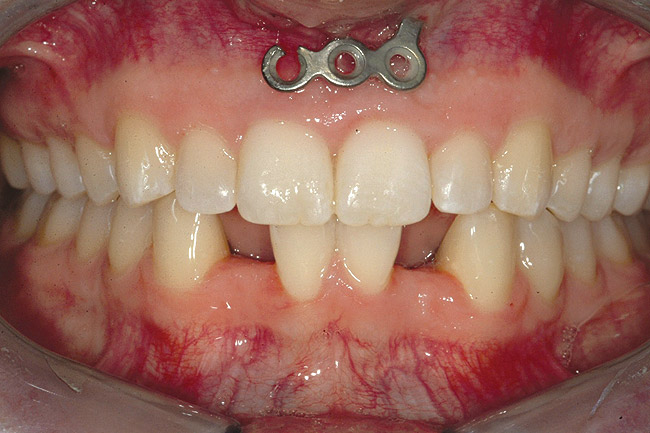

Fig 21 (and Fig 20). There is significant lateral dentoalveolar expansion of arches and alveoloskeletal correction in maxillary and mandibular anterior regions. Alveolar bone volume was increased in lower anterior to create optimal implant sites and establish ideal interincisal function and stability.

Fig 22 (and Fig 23). Final facial views show significant esthetic enhancements with broader maxillary arch, correction of “gummy smile,” and fuller lip support. Restorative dentist: John L. Garlinghouse, DMD.